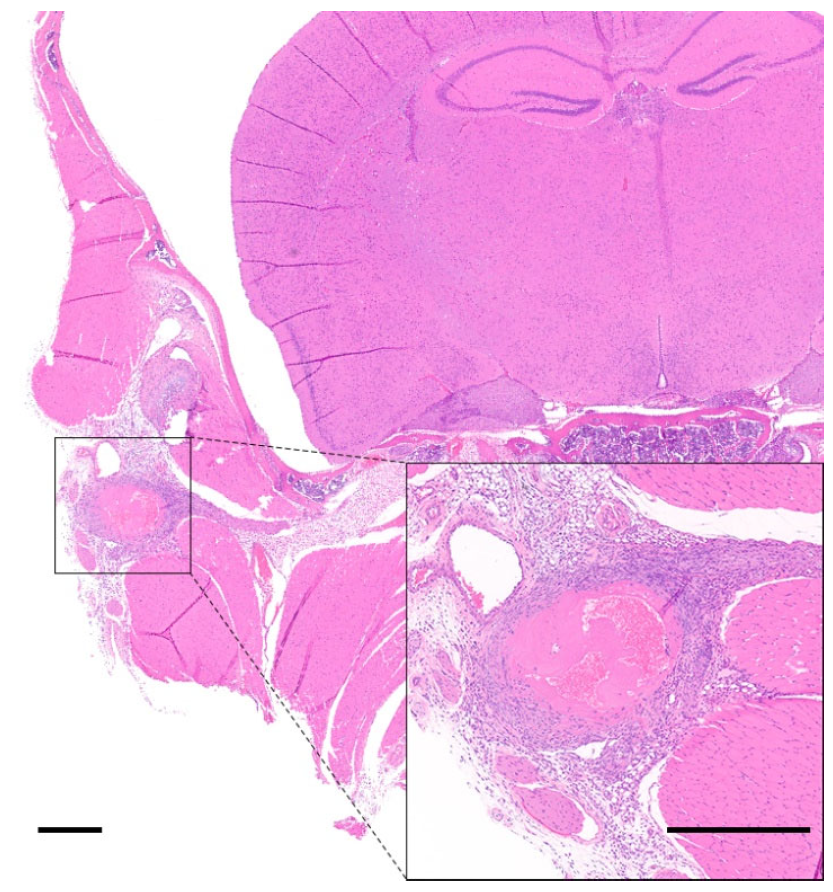

3.2. Lesions Associated with Manual Handling/Restraining

3.3. Blood Collection-Related Findings